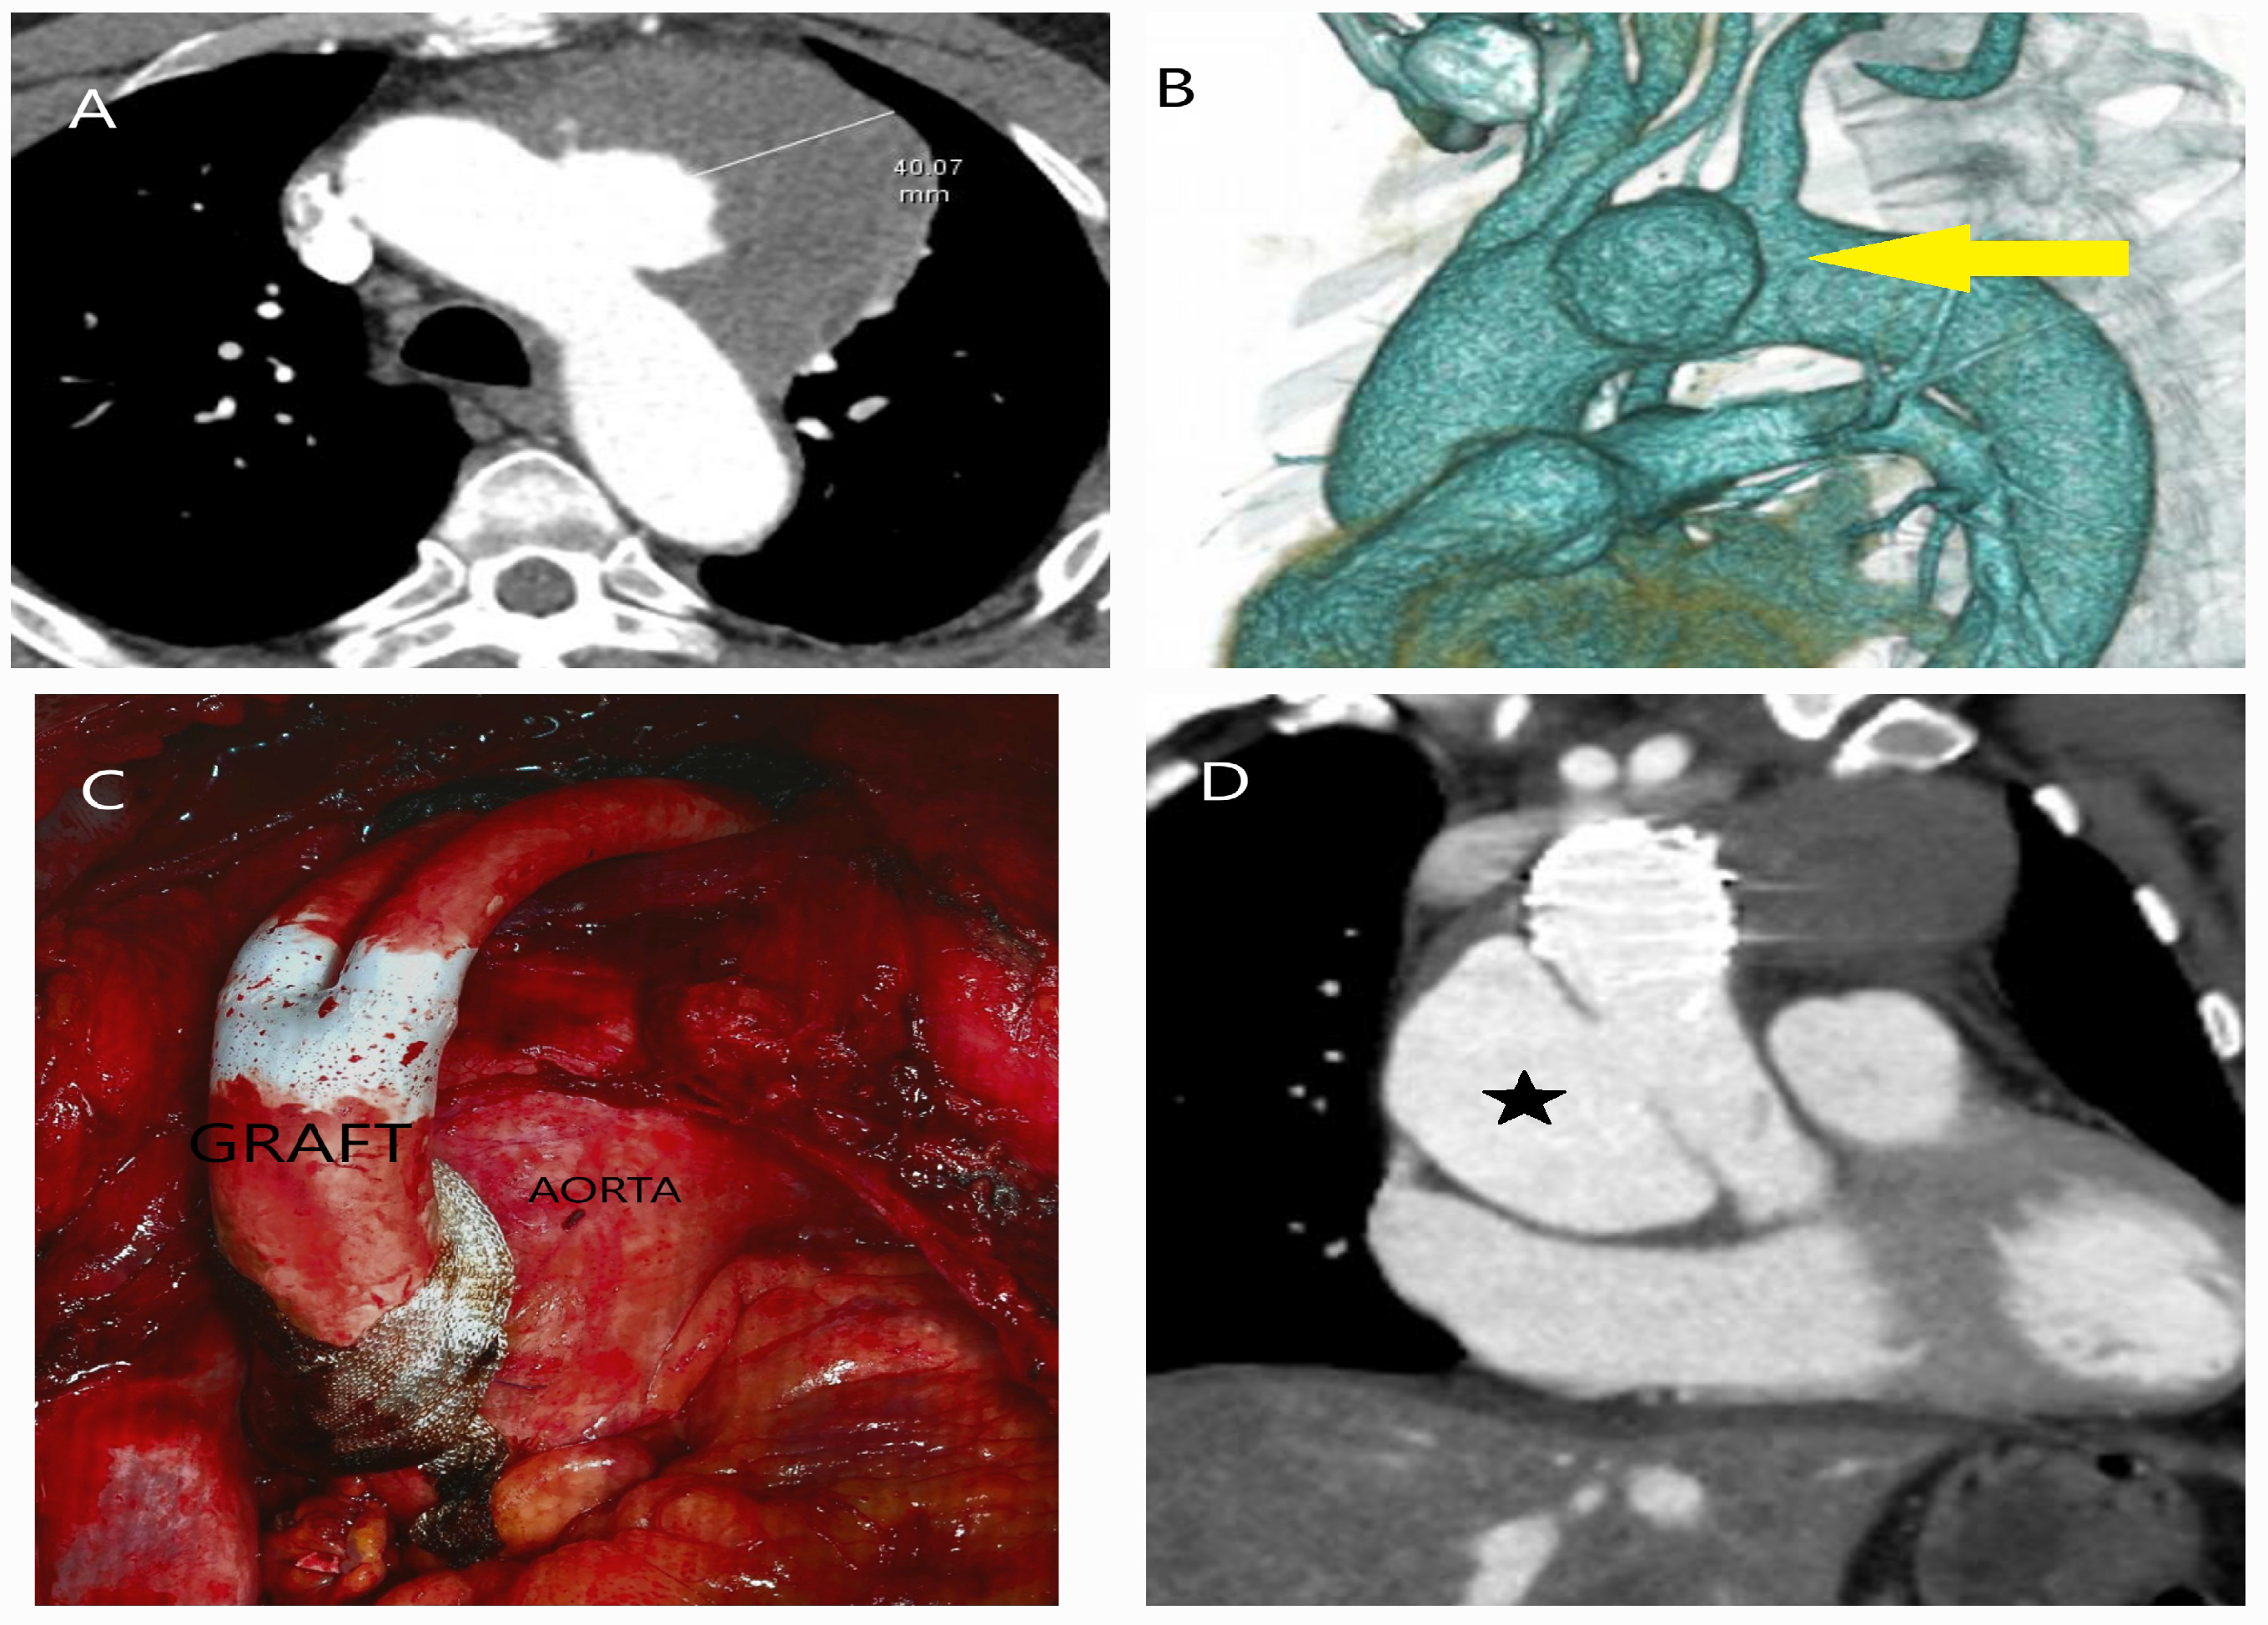

5.2.3. Computed Tomography